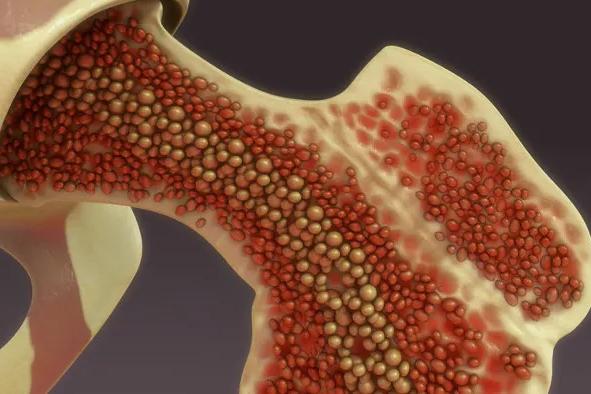

O que é medula óssea?

Também conhecida como 'tutano', a medula é um líquido-gelatinoso que ocupa a área interna dos ossos. Ela produz os principais componentes do sangue, como as hemácias, os leucócitos e as plaquetas

Pelas hemácias (glóbulos vermelhos), o oxigênio é transportado dos pulmões para todas as células de todo o organismo. Por outro lado, o gás carbônico é levado das células para os pulmões e é expelido.

Os leucócitos (glóbulos brancos) são os agentes mais importantes do sistema de defesa do organismo, combatendo infecções diversas.

As plaquetas ficam responsáveis pelo sistema de coagulação do sangue e, por ventura, da regeneração da área afetada.